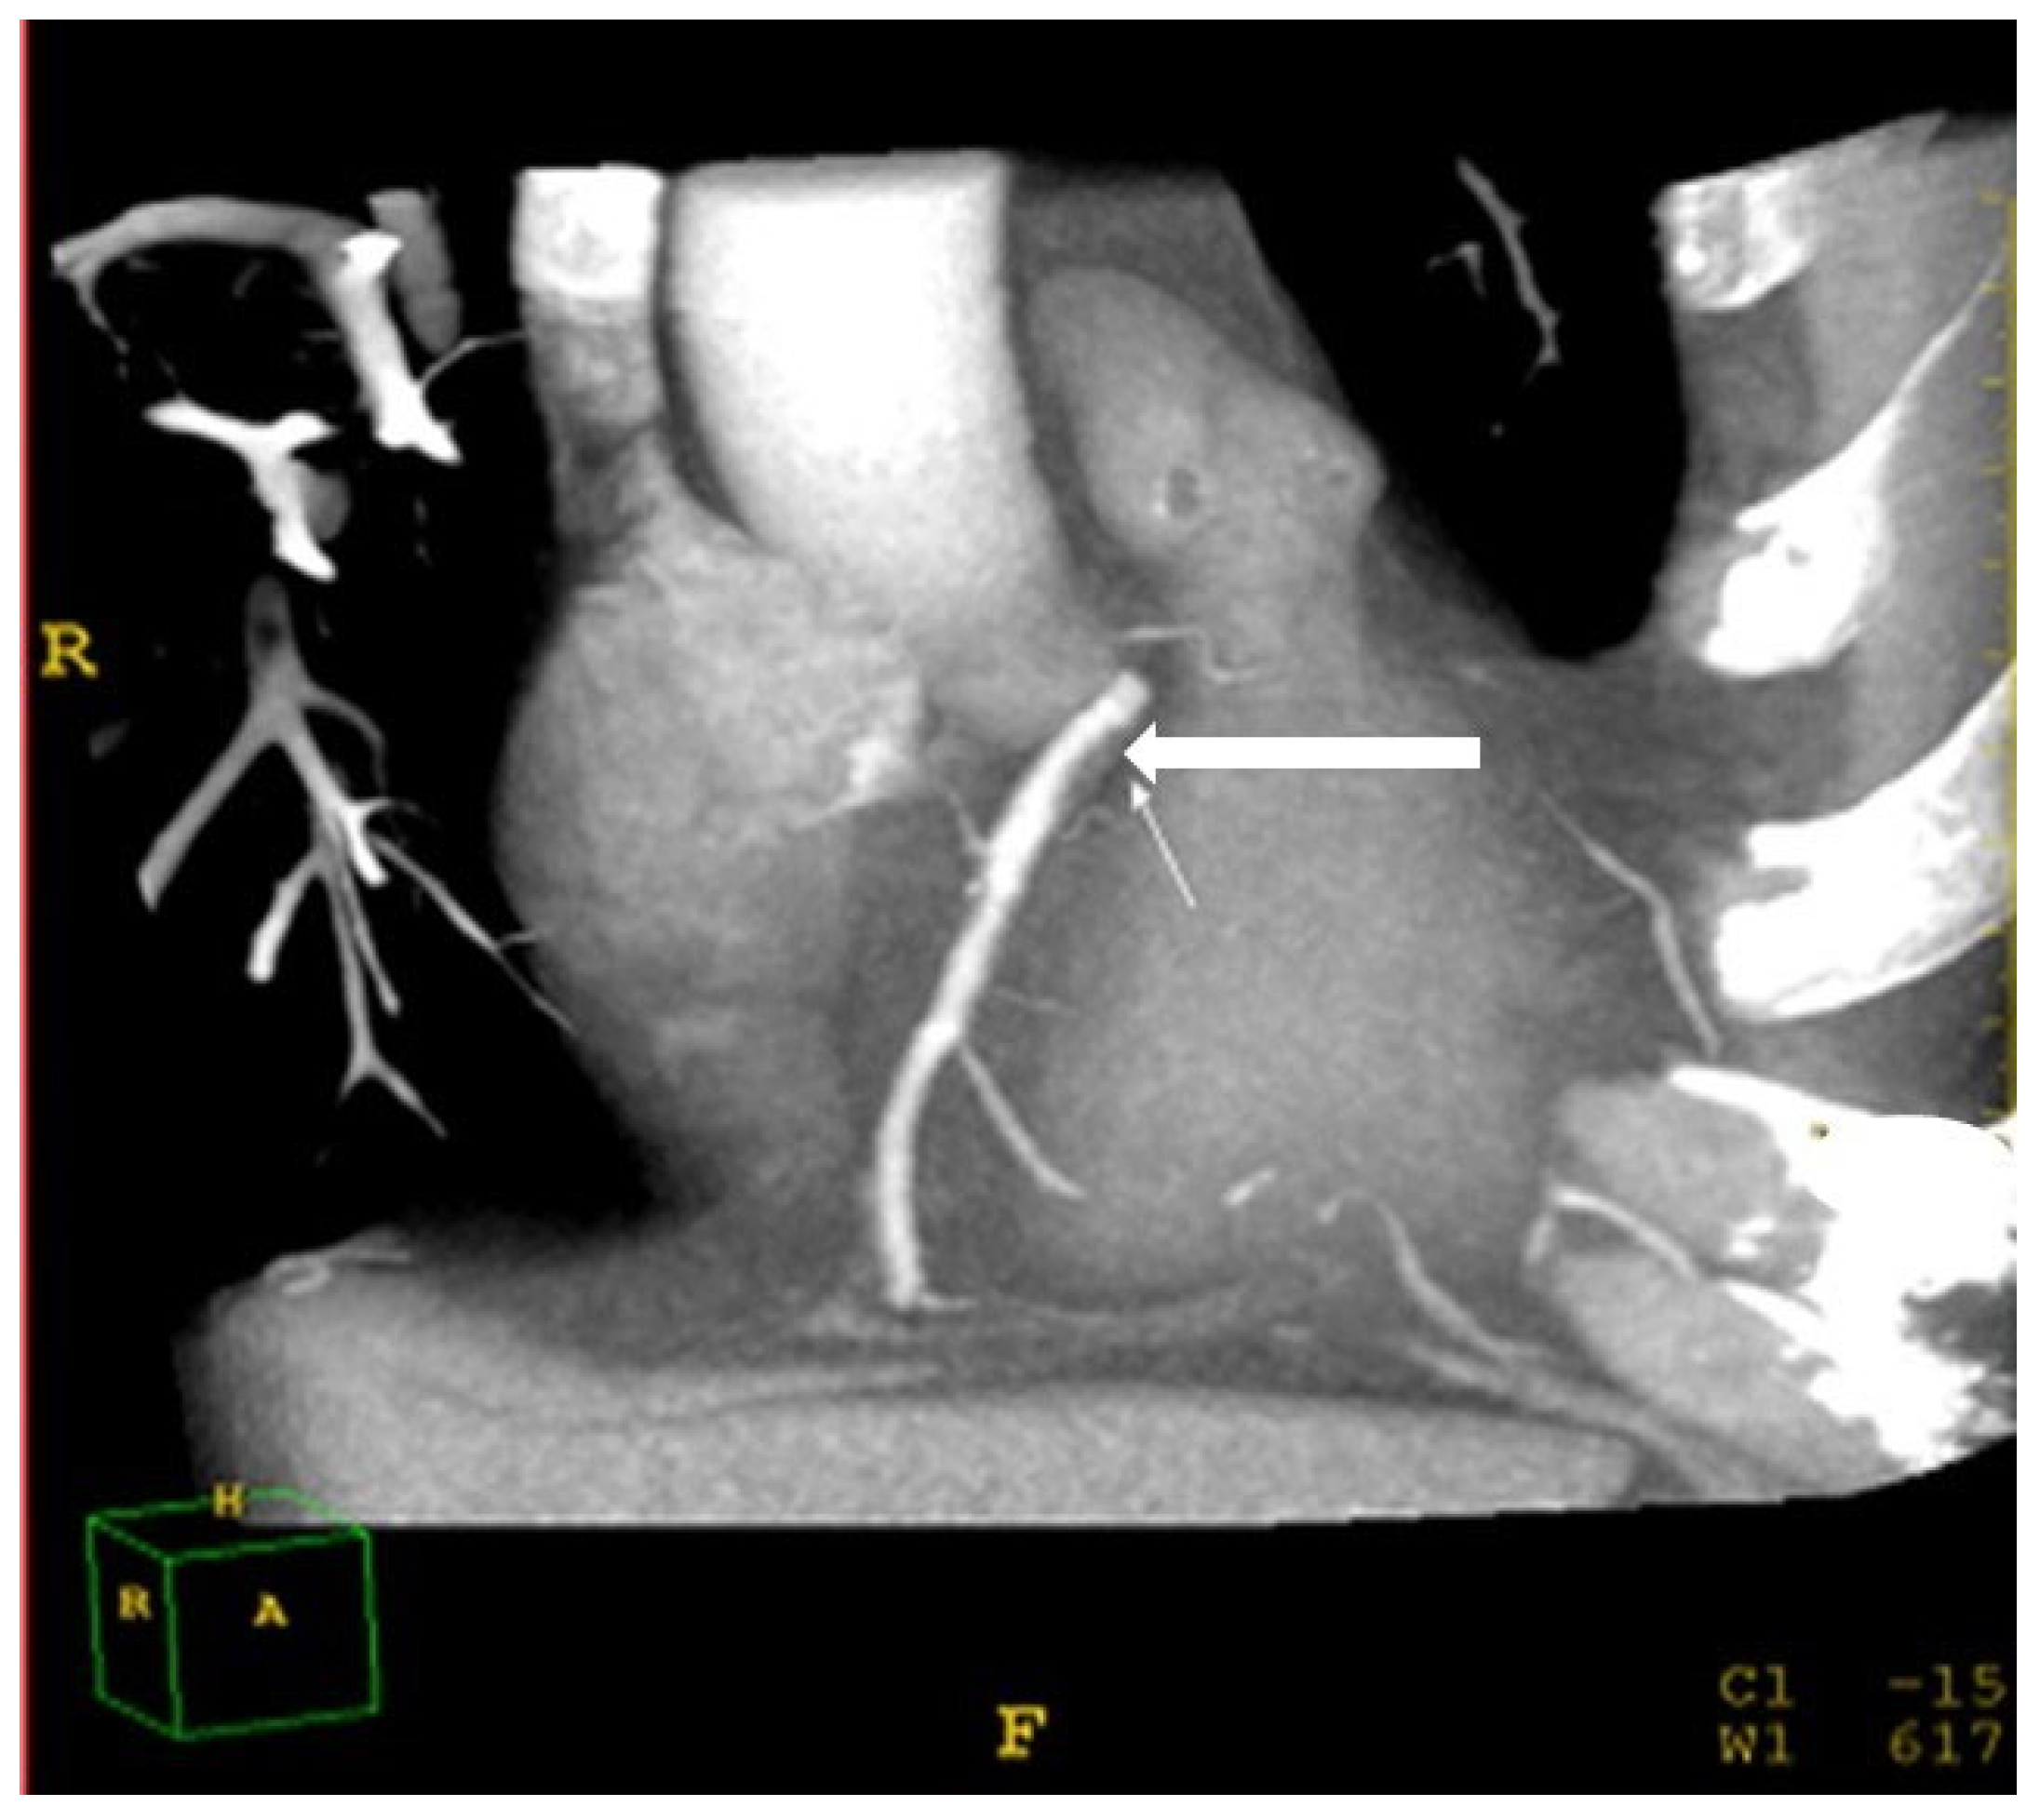

2.4. Hepatic Steatosis

Hepatic steatosis diagnosis was defined as attenuation of at least –10 HU (calculated as liver attenuation minus spleen attenuation) detected using CT [23]. The measurement of liver and spleen attenuation was performed in a blinded way. Hepatic attenuation was measured by randomly selecting three circular regions of interest (ROI) on three transverse sections at different hepatic levels. The ROI values were averaged as the mean hepatic attenuation. To provide an internal control, the mean splenic attenuation was calculated by also randomly averaging three ROI values of splenic attenuation on three transverse sections at different splenic levels (Figure 2).

Figure 2.

Computed-tomography section showing liver and spleen attenuation.

One limitation of the study is that the diagnosis of fatty liver was performed with non-enhanced CT rather than liver biopsy. However, a cutoff of liver–spleen density ≥ −10 HU identifies patients with diffuse fatty liver with 87% sensitivity and 90% specificity [23]. Another limitation is that fibro-scans and Fib-4 were not used in this research study, although other accurate tests were performed. The small number of the cohort in this single-center study warrants the further assessment of this issue in multi-center settings and with a wider cohort range.